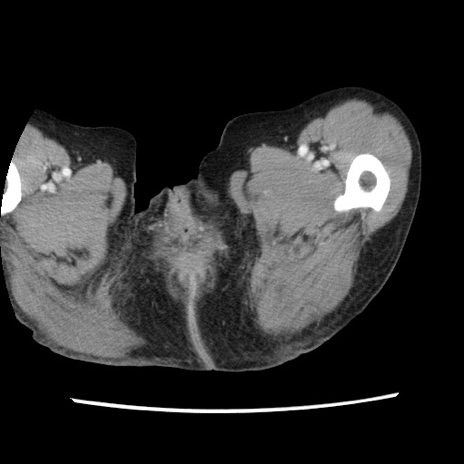

冠状断像

矢状断像